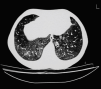

Fig. 1. Tomografía axial computarizada torácica de alta resolución en la que se aprecian áreas difusas de vidrio deslustrado bilateral, compatibles en el contexto clínico del paciente con hemorragia pulmonar.